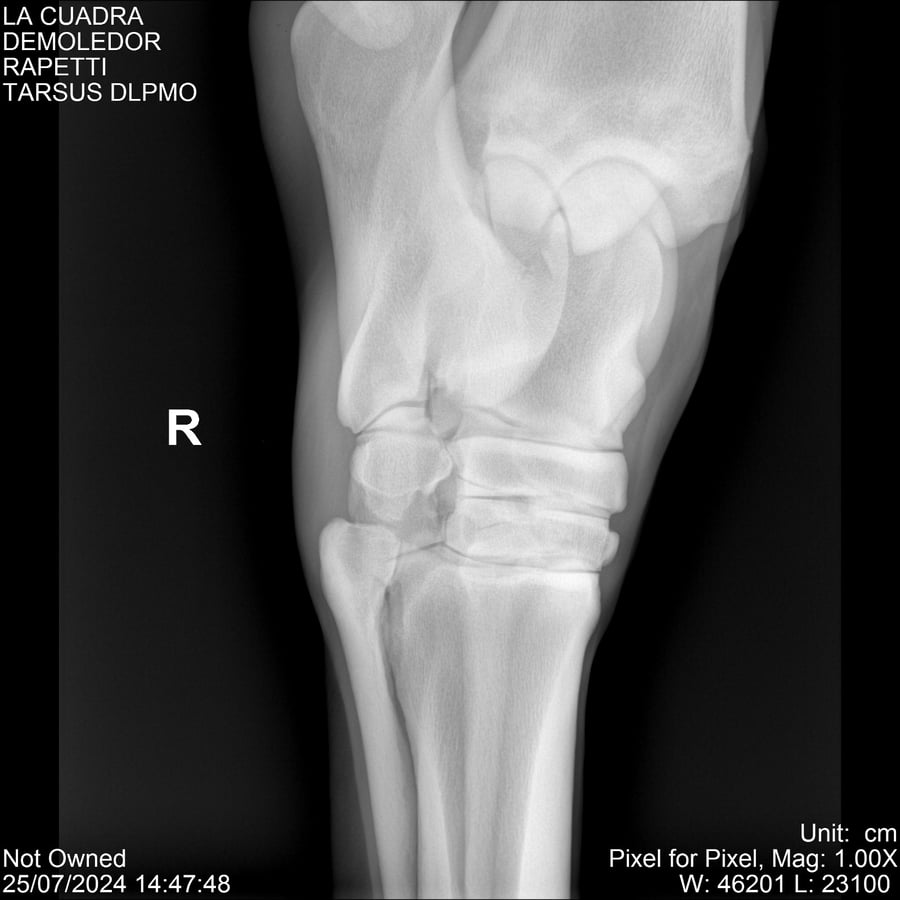

LOTE 14, DEMOLEDOR 🔥 🔥 🔥 Lote Anterior Volver al remate Lote Siguiente Ficha Contacto Montevideo - Ficha del Lote Identificador: #284454 Categoría: Yeguarizos Montevideo - 89 Visualizaciones ClicData Contacto Empresa: Abelenda N. R., Walter Hugo Nombre*: Teléfono* : E-mail* : Mensaje Enviar Registrese gratis Este contenido Exclusivo está disponible sólo para usuarios registrados Ingresar